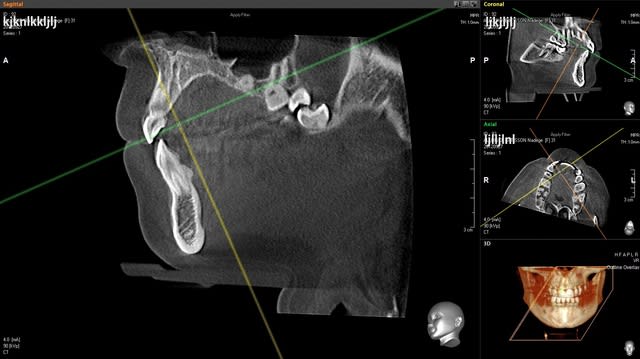

j' ai des coupes de chez morita

dés que je peux j'en mets de vatech

Capture morita 2 stjceh - Eugenol

Capture morita x66gah - Eugenol

Coupes morita fffknv - Eugenol

voila pour vatech,

le logiciel est beaucoup plus facile d'utilisation mais la précision laisse tout de même à désirer

Capture vatech s6ple1 - Eugenol

Capture vatech1 rivm62 - Eugenol

Capture vatech2 njn6uu - Eugenol